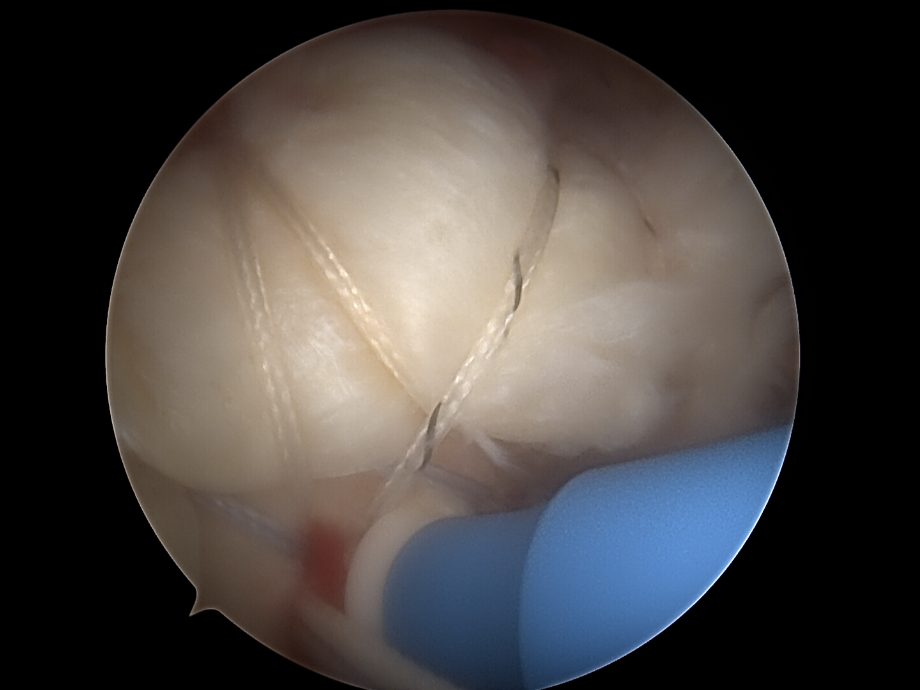

Naht und Refixation

• Verwendung von Fadenankern (Suture Anchors), die im Humeruskopf eingebracht werden. Die Sehne wird mit Fäden durchstochen und zur Knochenoberfläche zurückgeführt.

• Single-Row-Technik: Eine Reihe von Ankern entlang des Footprints.

• Double-Row-Technik: Zwei Reihen für breitere Kontaktfläche (höhere Stabilität).

• Suture-Bridge-Technik: Verbindung beider Reihen

subakromiale dekompression von dr. timmel von ortho-timmel.at